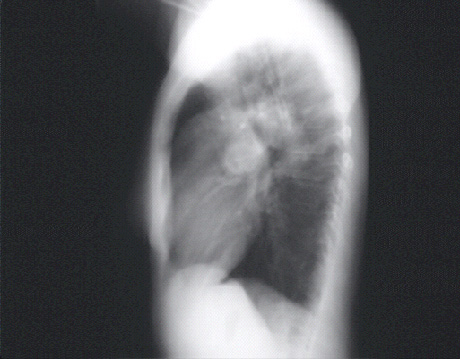

The lateral view confirms the markedly dilated pulmonary artery. Right ventricular enlargement is best seen in this view and is manifested by obliteration of the retrosternal air space.